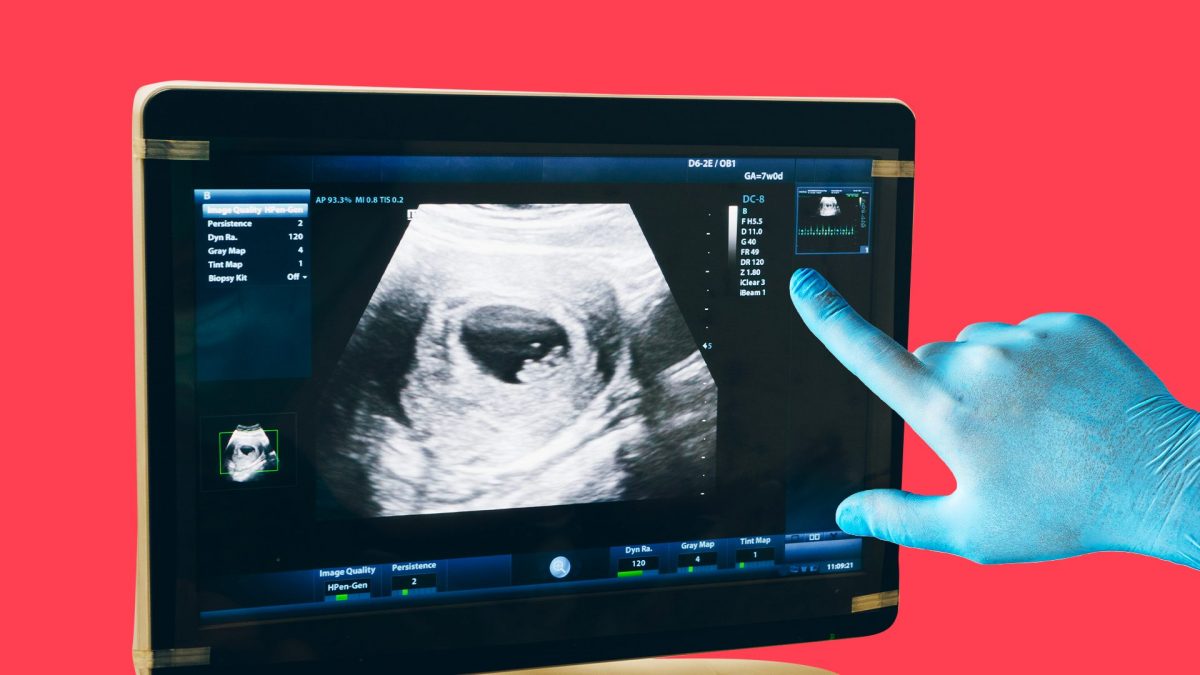

Come accennato, il sacco vitellino è visibile in ecografia, e quindi agli ultrasuoni, già dalla quinta settimana di gravidanza (soprattutto nel caso di ecografia transvaginale, e quindi interna). Lo si può osservare all’interno della camera gestazionale, che diventerà il sacco che accoglierà il bebè.

A quattro settimane dal concepimento (e quindi a sei settimane di gravidanza) il sacco vitellino è detto sacco vitellino definitivo, con il tubo intestinale che si collega all’embrione. In questo periodo le sue dimensioni si aggirano attorno ai 2 millimetri. Piano piano aumenteranno, fino ad arrivare ai 6 millimetri al compimento di dieci settimane.